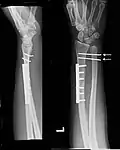

Die Therapie einer Galeazzi-Fraktur besteht in einer operativen Stabilisierung des Bruches durch Metallplatten und einer Ruhigstellung des distalen Radioulnargelenkes, beispielsweise durch kräftige Kirschnerdrähte. Eine direkte Naht des DRUG kann, muss aber nicht erfolgen. Anschließend muss der Arm im Oberarmgips in Supinationsstellung für 6 Wochen ruhiggestellt werden.[1]